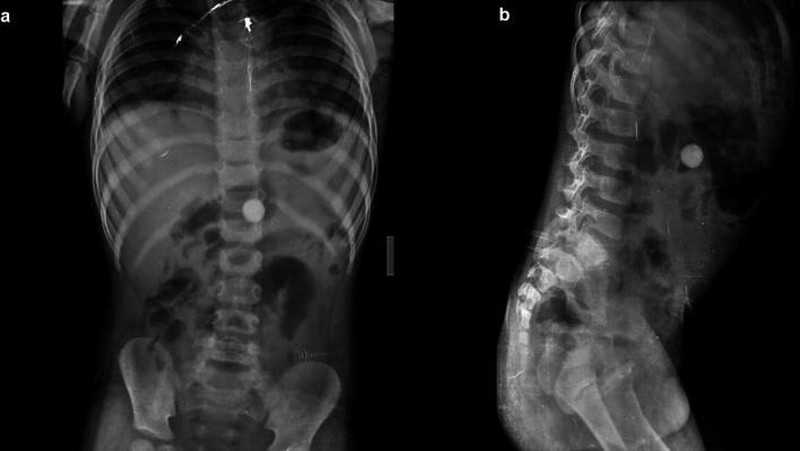

Seorang bocah empat tahun dilarikan ke rumah sakit karena mengalami nyeri perut selama 5-6 jam. Setelah dilakukan pemeriksaan, rontgen menunjukkan benda asing lingkaran berupa koin yang tidak sengaja tertelan. (Foto: F1000 Research)